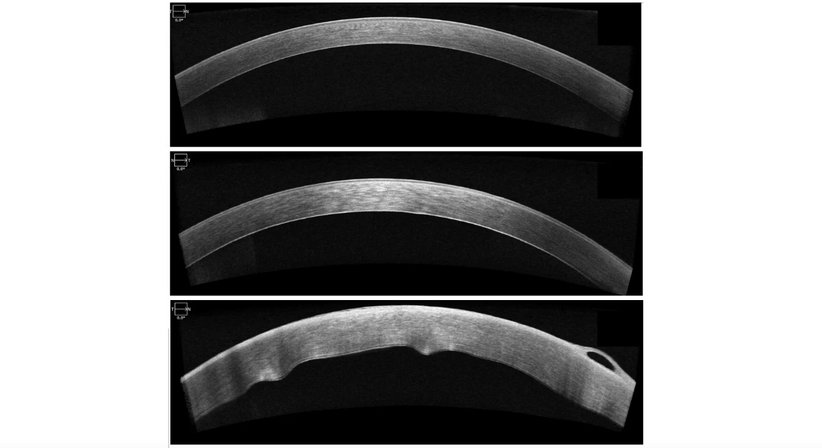

Hornhautnarben oder Unregelmäßigkeiten können ergänzend zur mikroskopischen Beurteilung am besten mittels hochauflösenden Laser-Schichtbildaufnahme (sog. OCT, optische Kohärenz Tomographie) untersucht und beurteilt werden. Auch dieses Messverfahren steht Ihnen in unserer Ordination zur Verfügung.